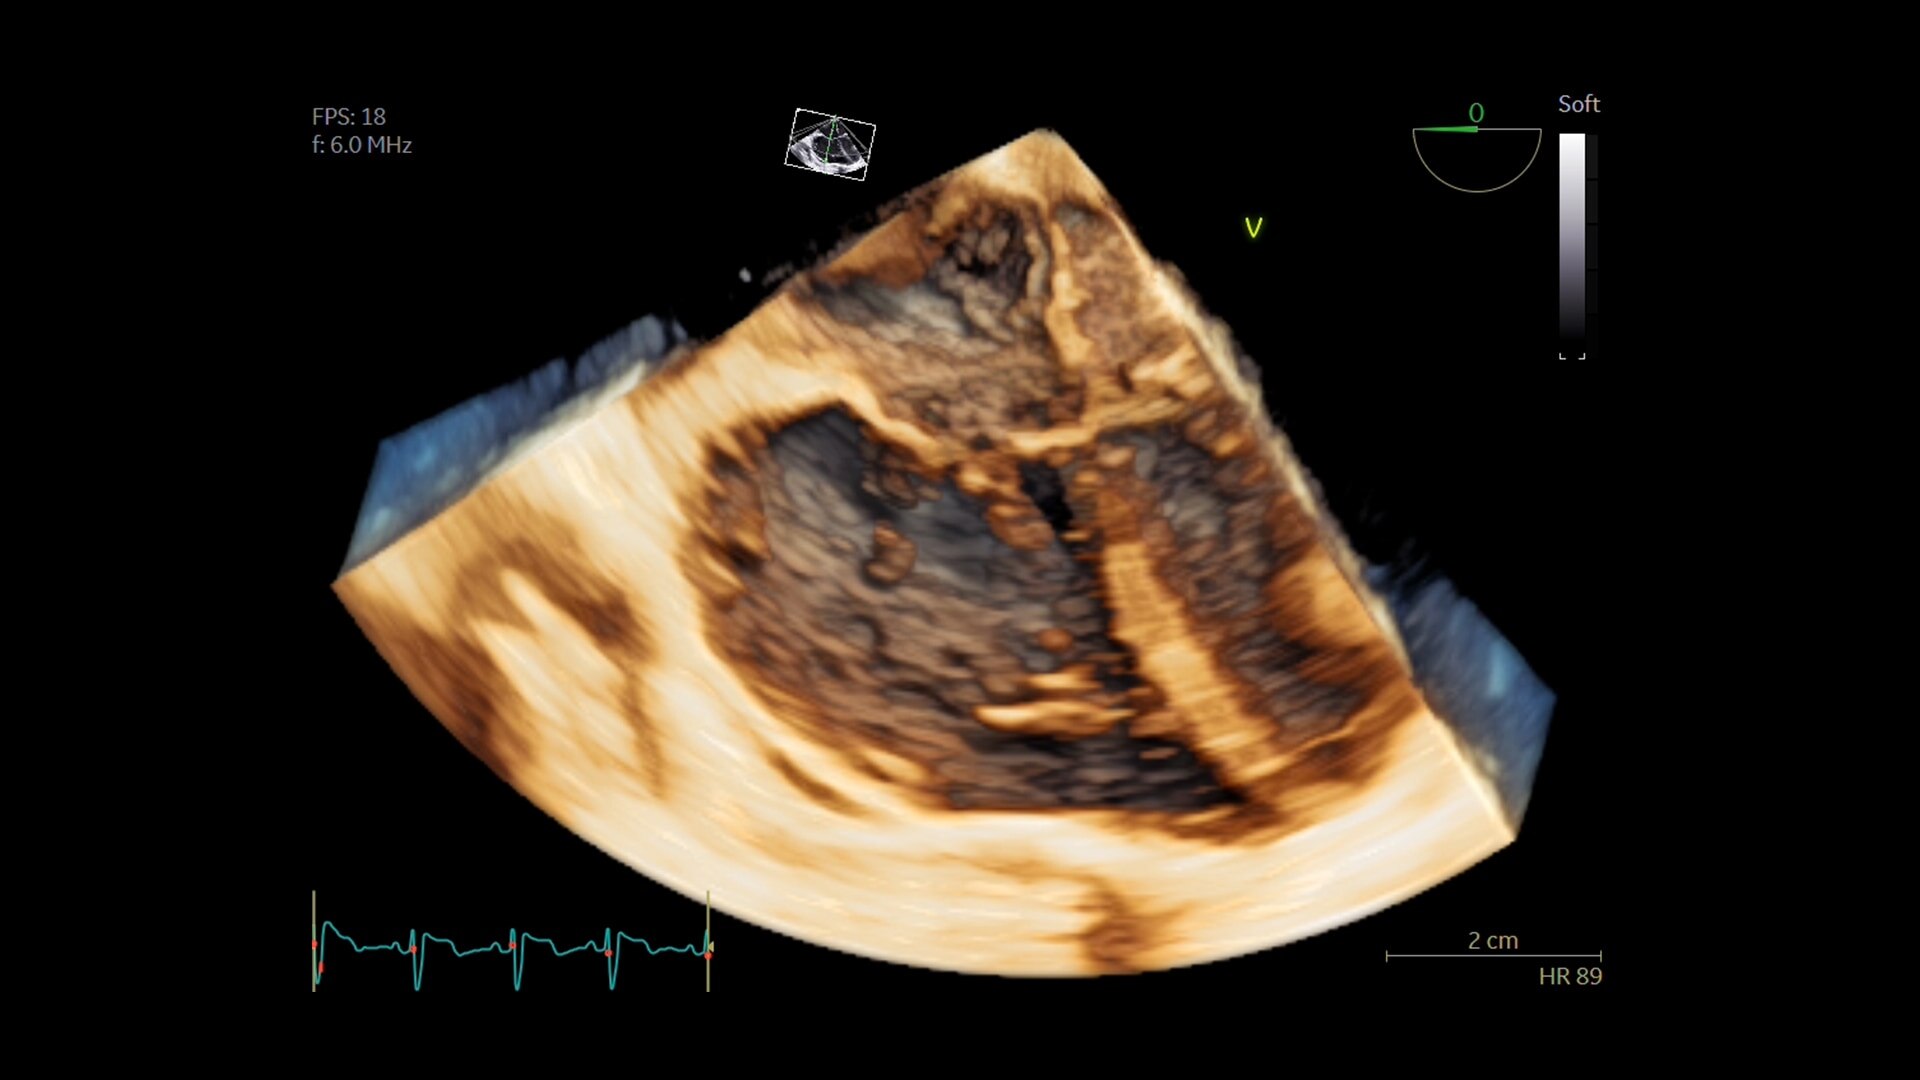

FE EM TEMPO REAL

Para resultados precisos, instantâneos e de atualização rápida

Capture resultados precisos instantaneamente sem exigir ECG—graças à FE em Tempo Real, uma ferramenta de IA que calcula de forma contínua a fração de ejeção durante escaneamento ativo em corte 4CH apical. E, para precisão melhorada, seu indicador de qualidade integrado ajuda os usuários a selecionar uma vista ideal para gerar resultados exatos. Reduza o tempo que leva para chegar a um resultado ao mesmo tempo em que ajuda a proporcionar consistência, um estudo descobriu que os resultados da FE em Tempo Real ficam dentro de ±10 pontos dos especialistas em 86% dos casos.²